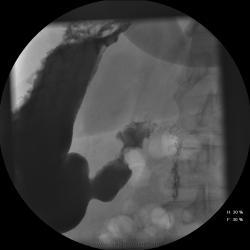

Женищина 49 лет, повышенного питания, обратилась с жалобами на потерю аппетита, жжение после чуть острой пищи, отрыжку с неприятным запахом, иногда темный стул, несколько похудела. Данные жалобы с сентебря-октября. Никуда не обращалась, коррегировала питанием. В последнее время стало хуже, обратилась...

Привратник удлиннен и ригиден, такое бывает при раке. Рек. ЭГДС.

Вы правы. я несколько недорасказал. женщина пришла уже с фгдс - инфильтративно-язвенный процесс в выходном отеде желудка у привратника по малой кривизне с переходом на переднюю стенку. так что прицельно смотрел этот отдел. перистальтка была ослаблена, краевой дефект в препилорической зоне по малой кривизне, передней стенке, кажущееся удлинение привратника, нависание основания луковицы - вообщем как в книжке. эвакуация было не изменена. написал рак выходного отдела желудка. вчера пришла гистология - высокодиф-я аденокарцинома. вот такая история.

Пока, касаясь только луковицы, но не препилорического отдела. "Ниши" в луковице есть, и они нуждаются в объяснении.

Конечно, в пилорическом канале уже растет, и "это" растет, уже и препилорической части и в луковице 12-ти перстной кишки.